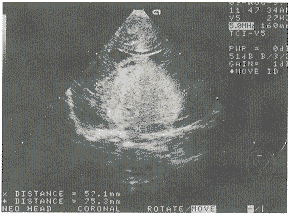

中国超声医学杂志991030 患儿男,1.5岁,不能独自站立、不会走。查体:神志清,智力反应差。背部有一1cm×1cm淡红色斑痣,面部无皮损。四肢活动不灵活,肌张力增高,膝反射活跃。超声检查:(前囟窗)脑中线居中,双侧侧脑室对称,前角扩大、变钝,宽1.1cm,脑中线到前角处侧壁距离2.4cm。颅组织回声均质。双侧侧脑室下方见一5.7cm×7.5cm×5.2cm圆形强回声光团,中心回声稍低。其内有不规则“小等号”状血管断面回声。边缘清晰,有线状高回声。不伴声影和声晕,后方无衰减(见图1)。彩色多普勒超声显示:内部及周边少许点状及斑片状色彩暗淡的血流信号。脉冲多普勒在肿物周边探及低速动静脉血流信号(见图2)。双侧大脑中动脉、左侧大脑前及大脑后动脉血流速度明显增高,收缩期、舒张期均增高。频谱形态正常,PI、RI、S/D正常。右侧大脑后动脉正常。未探及右侧大脑前动脉。超声诊断:颅内血管瘤。MRI证实为颅内巨大血管瘤。

图1 颅内巨大血管瘤